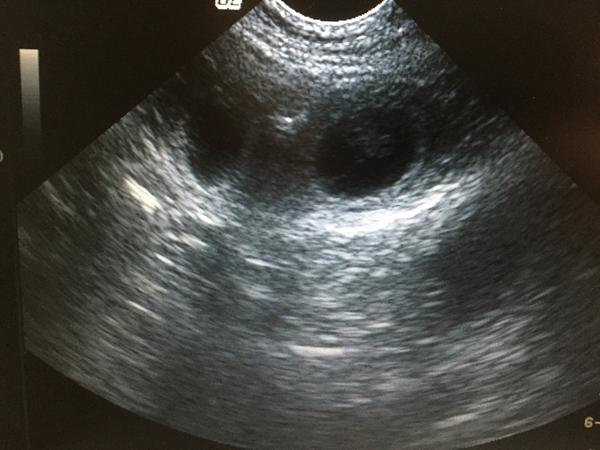

Hos Hund & Fys kan du få scannet din tæve for at få bekræftet om der er hvalpe på vej.

For at opnå det bedste resultat, scanner vi fra dag 28 efter sidste parring.